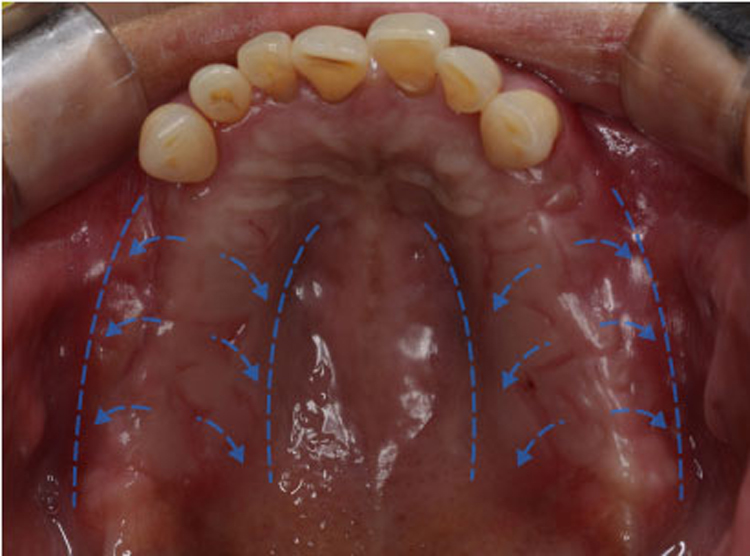

치료전 : 2018-08-16